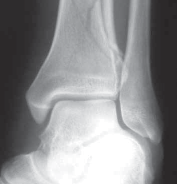

5.

The diagnosis of tibial plafond fracture is initially evaluated with three radiographic views of the ankle (anteroposterior [AP], mortise, and lateral; FIG 4A,B).

CT scans have been clearly shown to improve a surgeon’s understanding of the injury ( FIG 4C) and are critical to preoperative planning for complex injuries.15

7.

For displaced, comminuted pilon fractures, the best time to obtain a CT scan is after temporizing external fixation is performed ( FIG 4D), when the fracture is brought out to length with traction. This tends to grossly reduce many parts of the fracture, making the pathoanatomy of the injury more understandable (FIG 4E,F).

E F ### FIG 4 • 43-C3 tibial plafond injury. A,B. AP and lateral injury radiographs. C. CT scan. D. “Travelling traction”—early ankle-spanning external fixator. E,F. Radiographs of ankle after closed reduction and application of external fixator. G. Three-dimensional reconstruction of CT angiogram demonstrat- G ing deficient flow through anterior tibial artery.